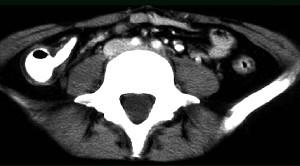

问题 女,32岁,腹痛、腹泻、便秘交替出现,黏液血便半年,里急后重,影像检查如图,最佳的诊断是 ( )

选项 A、溃疡性结肠炎 B、肠结核 C、慢性结肠炎 D、过敏性结肠炎 E、结肠癌

答案 A